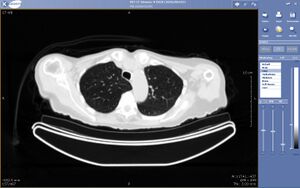

يمكن تعريف التطبيب عن بعد، أو الطب البعادي Telemedicine، على أنه نقل البيانات الطبية الإلكترونية (الصور، الأصوات، أفلام الفيديو، سجلات المرضى عالية الوضوح) من مكان إلى مكان آخر، من أجل صحة المريض وتعليمه أو مقدم الخدمة الصحية، وبغرض تحسين رعاية المرضى.

ويستخدم التطبيب عن بعد من قبل مقدمي الرعاية الصحية في عدد متزايد من التخصصات الطبية، بما فيها طب الجلد، وطب الأورام، والأشعة، والجراحة، وطب القلب، والطب النفسي، والرعاية الصحية المنزلية.

2- التطبيب عن بعد بالتخزين والإرسال :Store & forward وهو التقديم المتزامن للخدمات الطبية. وفي عالم اليوم، يتخذ ذلك شكل رسالة بريد إلكتروني بالوسائط المتعددة multimedia e-mail ترسل إلى طبيب استشاري بواسطة إحدى خدمات الاتصالات الإلكترونية، ومنها الإنترنت. ويقوم الطبيب الاستشاري بمراجعة البيانات المرسلة إليه، ومن ثم إرسال رأيه بنفس الطريقة إلى المريض في المناطق النائية. وتفيد هذه الطريقة بصورة أساسية في الحالات الطبية غير الطارئة.

3- التطبيب عن بعد بالمؤتمرات الفيديوية Video conference Telemedicine: وهو نمط آخر من التقديم المتزامن للخدمات الطبية، ويتخذ شكل مؤتمر فيديوي مباشر بين المريض و «مقدم حالته» (عادة مايكون طبيب الرعاية الصحية الأولية الذي يعالجه)، وبين طبيب استشاري في مستشفى رئيسي، حيث يقوم الطبيب الاستشاري بمراجعة البيانات المتعلقة بالمريض قبل عقد المؤتمر الفيديوي، ومن ثم يجري المؤتمر الفيديوي على الهواء، وبعد ذلك يرسل تقريرا مكتوبا عن رأيه في الحالة.